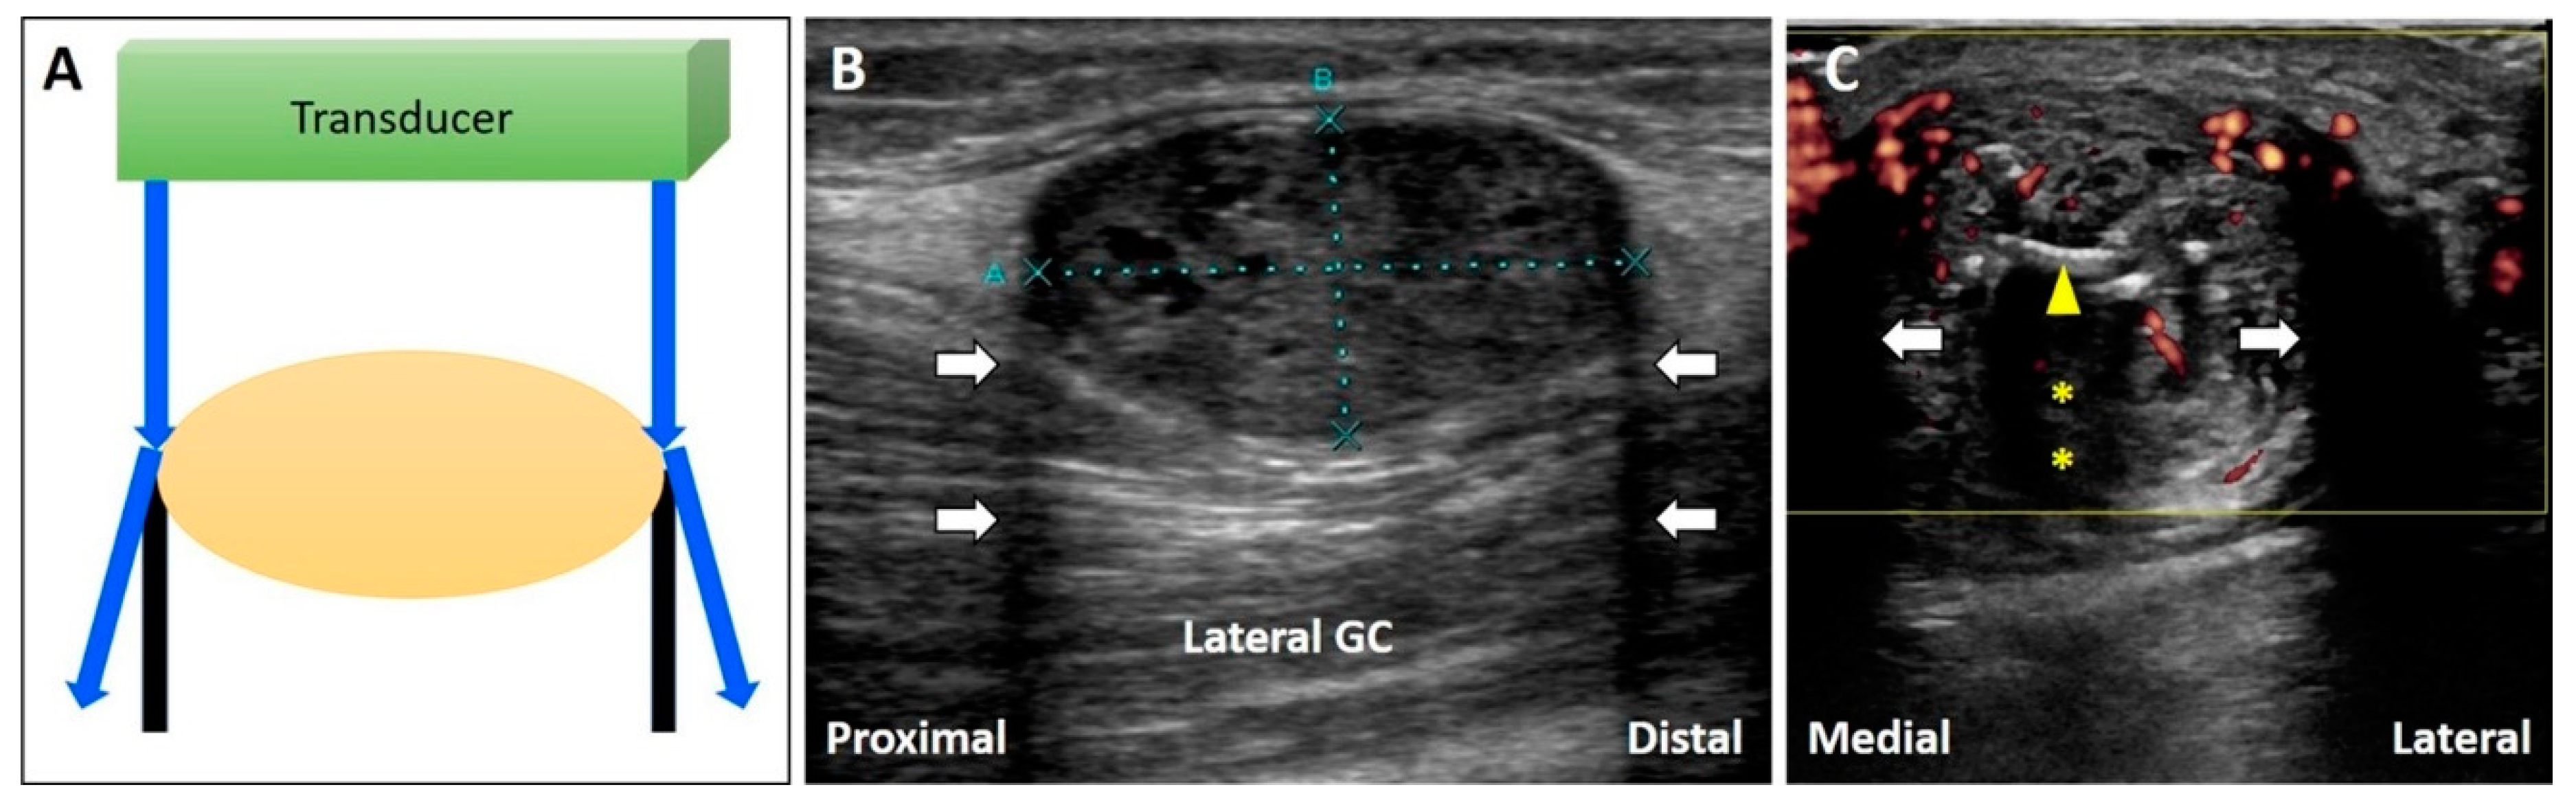

When the US beam hits the edge of a curved surface, most of the US beam is reflected away from the transducer, appearing as hypoechoic parallel lines projecting along the edges of the target (Figure 13A).

Figure 13.

Schematic drawing illustrates the hypoechoic parallel lines projecting along the edges of the curved structure because most of the US beam is reflected away from the transducer (A). The edge artifact can be observed at the edges of a circular structure, such as a schwannoma of the lateral sural cutaneous nerve (B). This artifact may be misinterpreted as thickened Achilles paratenon (C). White arrow: edge artifact; yellow arrowhead: sutures; yellow asterisk: acoustic shadowing due to sutures. GC: gastrocnemius muscle.

4.2.2. Clinical Examples

This artifact can be observed at the edge of a circular structure, such as a schwannoma of the lateral sural cutaneous nerve (Figure 13B). During scanning of a patient with Achilles tendinopathy (Figure 13C), the artifact may be misinterpreted as a thickened paratenon. Adjusting the angle of insonation (e.g., heel-toe maneuver) can circumvent the artifact.